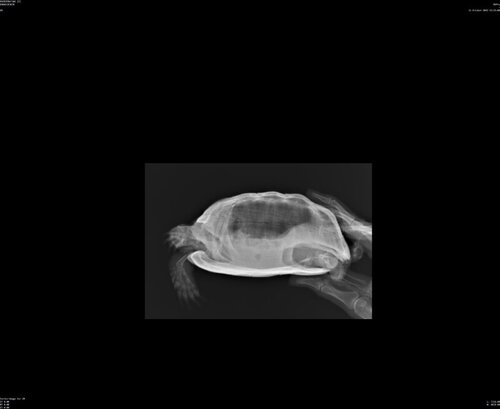

Обратились в клинику. Сделали рентген, доктор сказала, что ничего не насторожило. Есть немного обезвоживание. Кровь пока не сдавали. Когда посмотрела горло, сказала, что там налет. И выписали Байтрил 5%, по 0,04мл каждый день 14 дней. И раствор Рингера  8мл раз в два дня 7 дней. Можно ли прокомментировать назначение? Т.к. на форуме говорится, в основном,  о Байтриле 2,5%, и не каждый день. Пока поставили в клинике один раз, и два раза я дома. Но, похоже, не разобралась со шприцом, поставила оба раза по 0,02мл, а не 0,04мл

Врача звали Морозова Валерия Сергеевна. Ничего плохого сказать не могу, черепаху смотрели очень внимательно. Сначала он никак не хотел открывать рот. Посмотрели на рентгене, ничего страшного не увидели. Нам предложили дополнительно сдать кровь, но я сразу не была готова. Тогда решили, что еще понаблюдаем. Т.к. предположили, что не хватает УФ, потому что лампу мы только накануне приобрели. И под конец приема удалось заглянуть ему в рот. И Валерия Сергеевна сказала, что там все с налетом. Предположила инфекцию. И сказала, что с таким горлом уже сразу назначает антибиотик. Тем более, он сразу и запищал, как горло задели. А уж сдавать кровь или нет - это наш выбор. Я просто сомневаюсь насчет Байтрила 5% - сколько в итоге колоть? Если по 0,04мл, то это через день тогда? 14 уколов? Или лучше все-таки купить 2,5%? Тогда по сколько колоть?